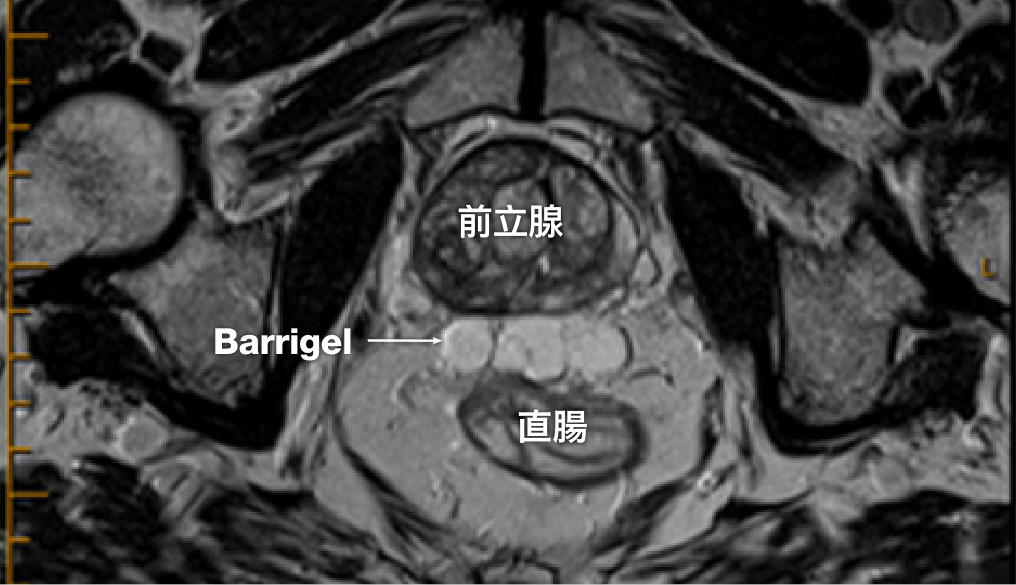

MR 画像

MR画像提供:Prof Michael Chao, MBBS (Hons), FRANZCR, AFRACMA, DMedSc, Radiation Oncologist; Victoria, Australia